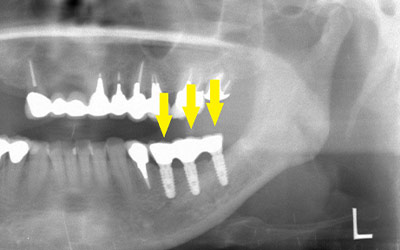

患者様の治療前のレントゲン写真です。写真の黄色矢印部の歯の周囲は、重度の歯周病で大きく歯槽骨が吸収されてしまっていました。そのため、写真の、赤色矢印で示す、下顎骨の中を通る神経までの距離がなく、インプラント埋入には、骨の高さが不足していました。

重度の歯周病の歯を抜歯して、インプラント治療を行う予定となりました。

インプラントを埋入するためには、骨を増やさなければならず、患者様ご自身の骨を移植する、自家骨移植術を行なうこととしました。写真、青色の矢印で示す、智歯周辺の骨を採取し、黄色の矢印の部位に骨片を移植、チタン製の小さなスクリューで骨片を固定するという手術を行いました。細く、白く映っているのが骨を固定したミニスクリューです。

インプラント埋入後のレントゲン写真です。骨の高さが十分に確保されたので、神経を傷つけることなく、安全にインプラント埋入手術ができました。